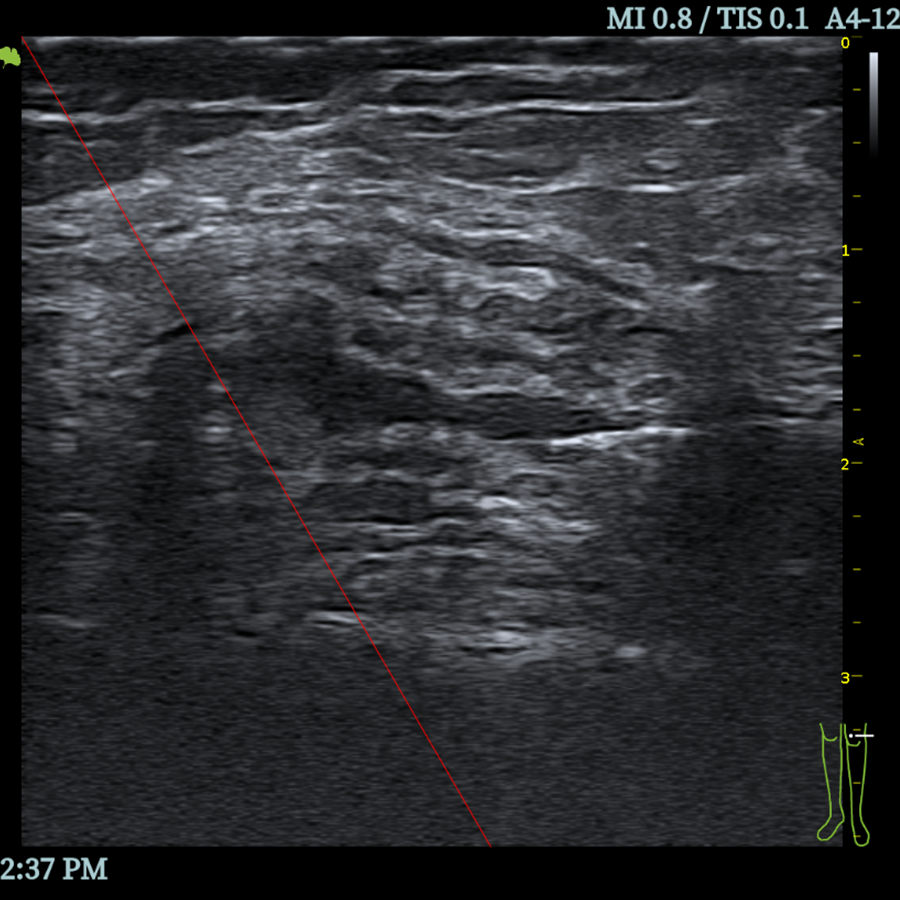

- Guía de Biopsia